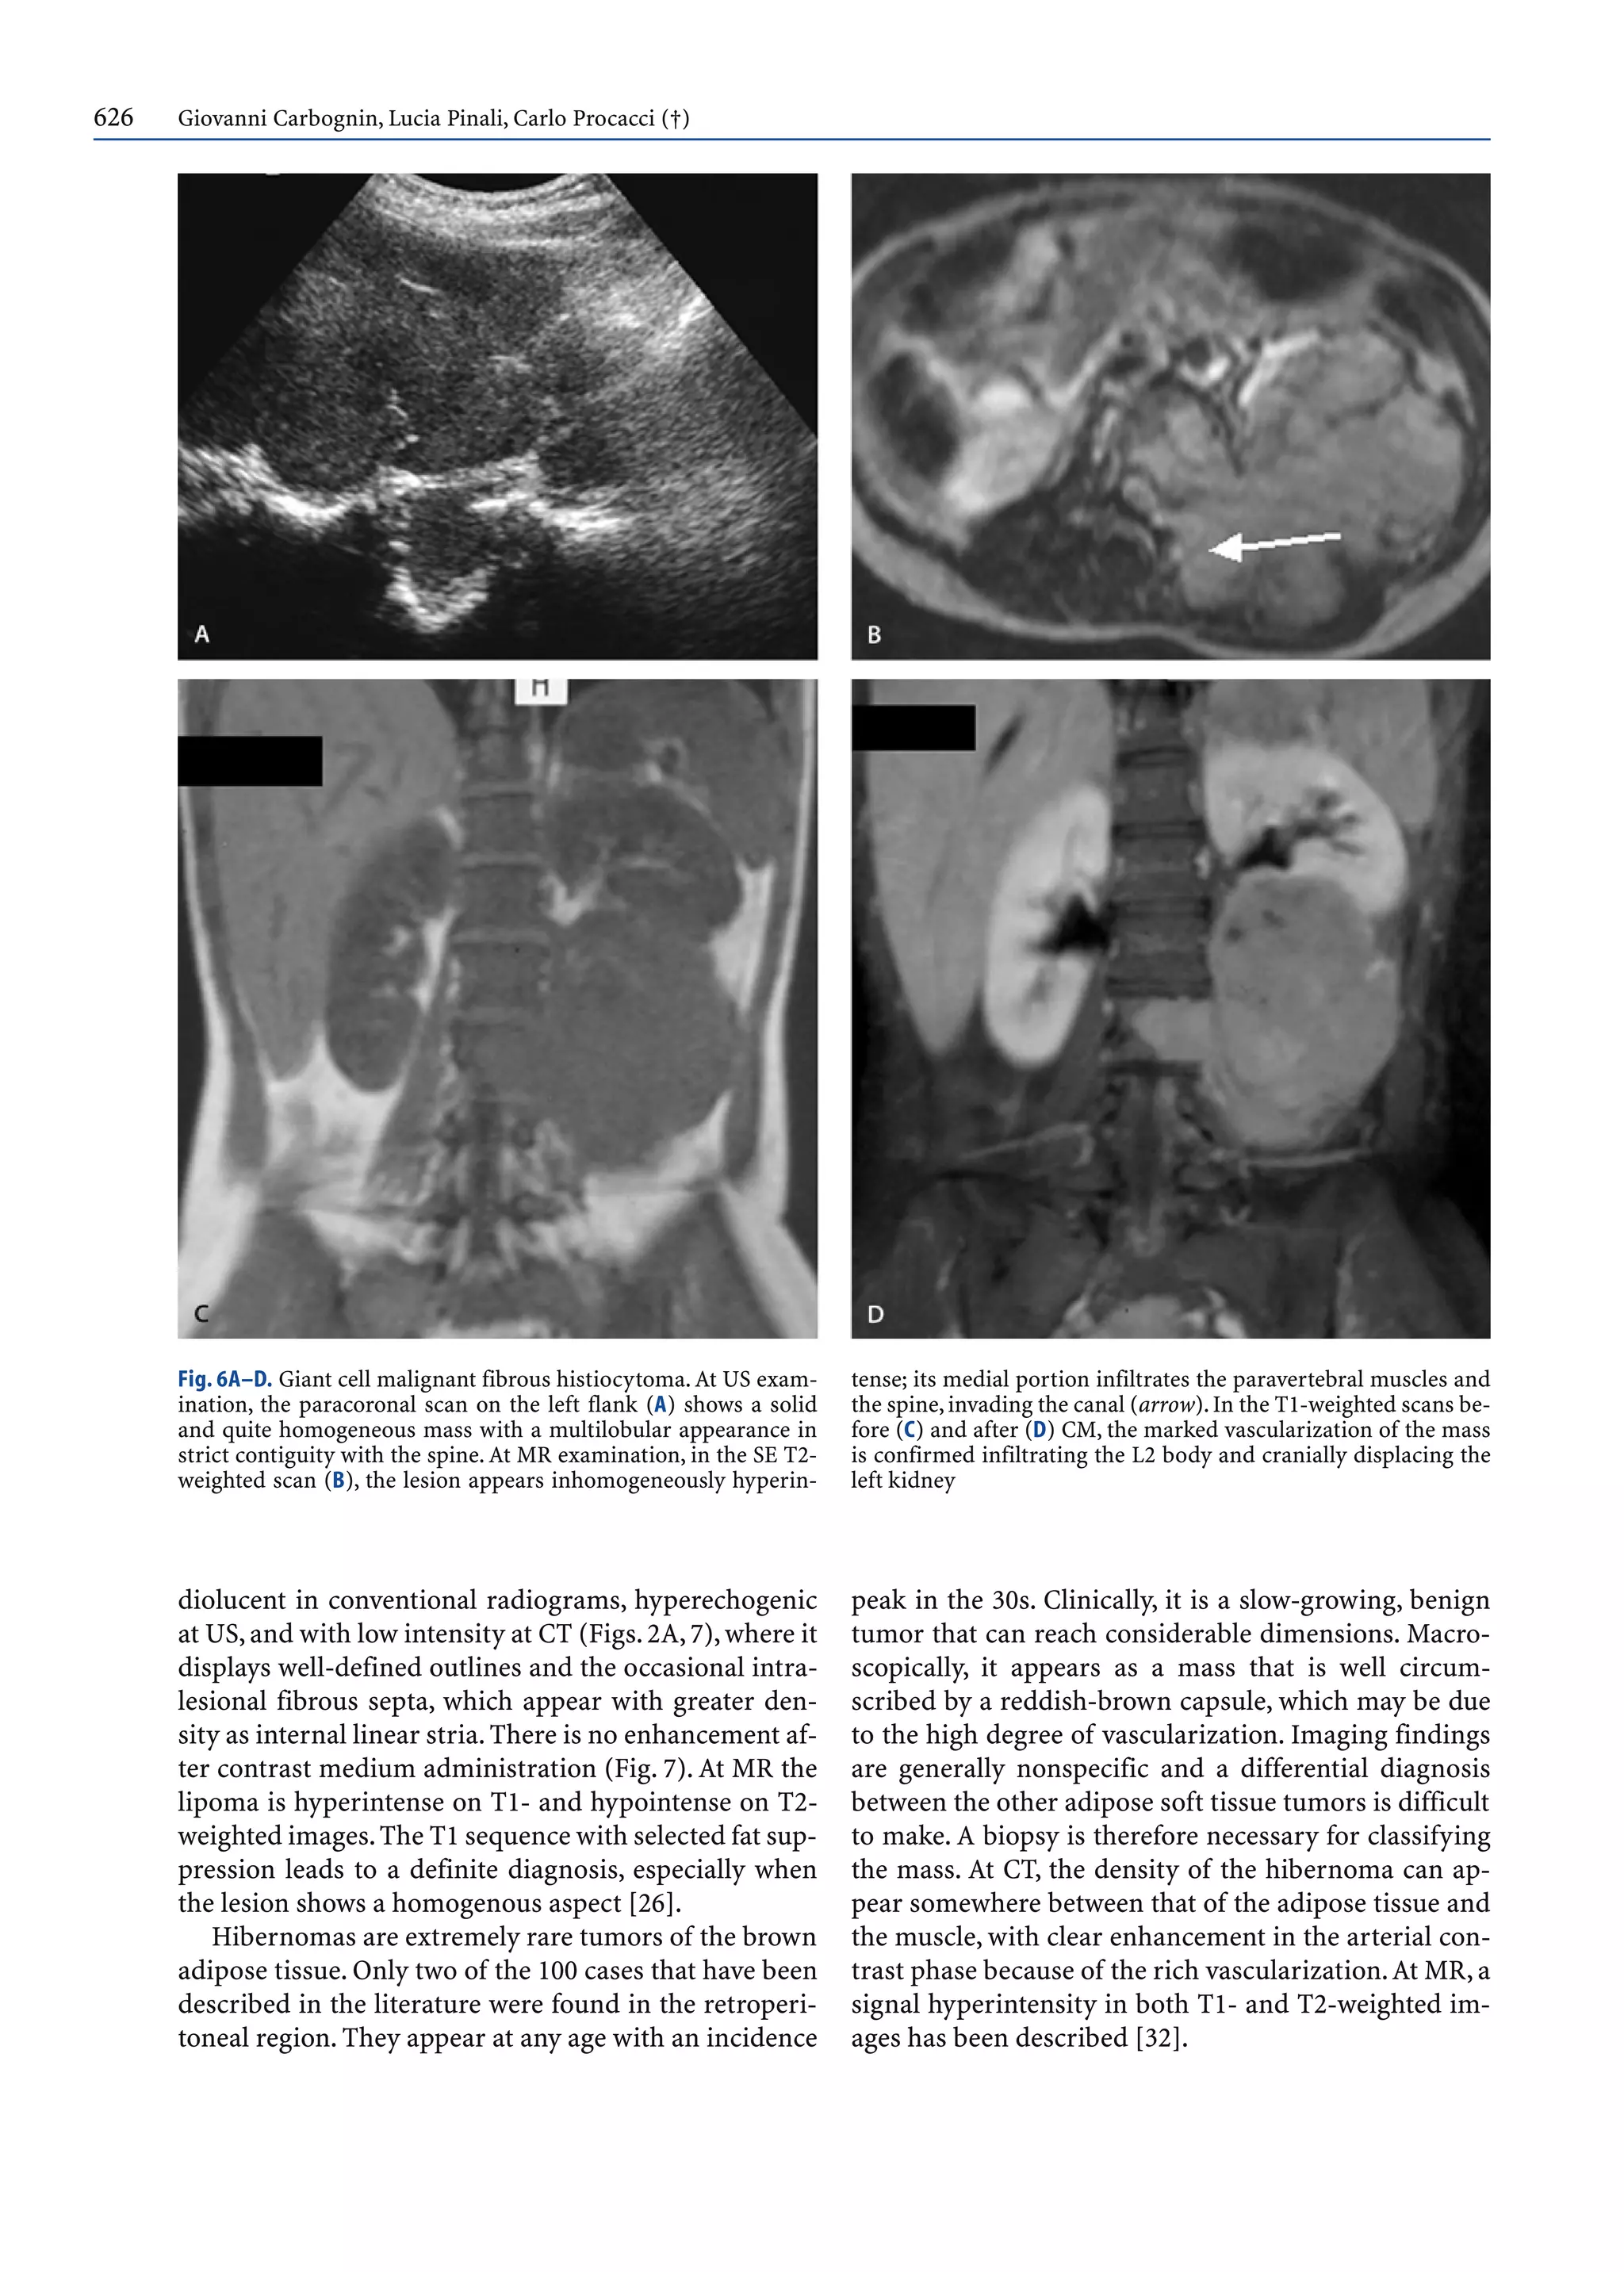

At imaging it appears with the typical characteristics

of a fatty, hypovascularized mass: homogeneously ra-

626 Giovanni Carbognin, Lucia Pinali, Carlo Procacci (†)

diolucent in conventional radiograms, hyperechogenic

at US,and with low intensity at CT (Figs.2A,7),where it

displays well-defined outlines and the occasional intra-

lesional fibrous septa, which appear with greater den-

sity as internal linear stria.There is no enhancement af-

ter contrast medium administration (Fig. 7). At MR the

lipoma is hyperintense on T1- and hypointense on T2-

weighted images.The T1 sequence with selected fat sup-

pression leads to a definite diagnosis, especially when

the lesion shows a homogenous aspect [26].

Hibernomas are extremely rare tumors of the brown

adipose tissue. Only two of the 100 cases that have been

described in the literature were found in the retroperi-

toneal region. They appear at any age with an incidence

peak in the 30s. Clinically, it is a slow-growing, benign

tumor that can reach considerable dimensions. Macro-

scopically, it appears as a mass that is well circum-

scribed by a reddish-brown capsule, which may be due

to the high degree of vascularization. Imaging findings

are generally nonspecific and a differential diagnosis

between the other adipose soft tissue tumors is difficult

to make. A biopsy is therefore necessary for classifying

the mass. At CT, the density of the hibernoma can ap-

pear somewhere between that of the adipose tissue and

the muscle, with clear enhancement in the arterial con-

trast phase because of the rich vascularization.At MR, a

signal hyperintensity in both T1- and T2-weighted im-

ages has been described [32].